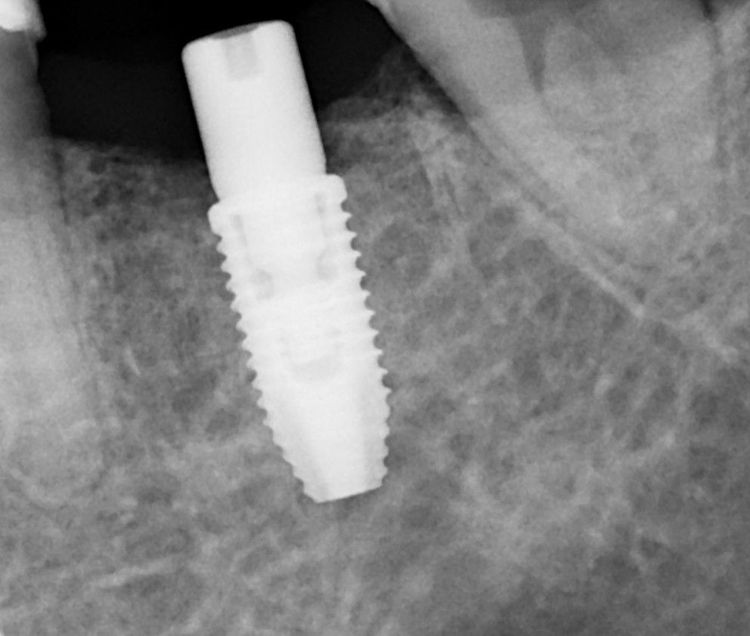

Через два месяца, после оценки состояния тканей, была выполнена установка дентального имплантата системы Nobel Biocare. Одновременно была проведена мягкотканевая пластика с целью улучшения анатомии будущей коронковой зоны. На имплантат установлен формирователь десны — временный компонент, необходимый для создания физиологического и эстетически благоприятного профиля прорезывания.